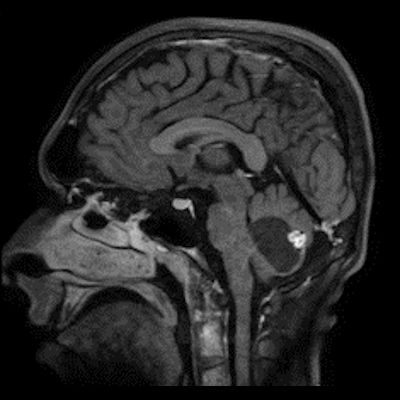

24 yaş, E

Baş ağrısı

4.ventrikül tabanına oturmuş posterior fossada hemanjioblastoma

bilateral vestibuler schwannoma ve kist duvarı kontrastlanmaması nedeniyle hemangioblastom ancak yeri itibariyle pilositik astrositom ayırıcı tanısı

PİLOSİTİK ASTROSİTOMA